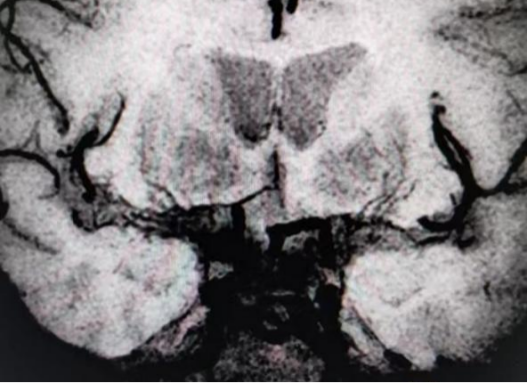

2招丨鉴别烟雾病起因

4a3f949703afaff49bceeb50c8e42009.png6f8e0e6e18d899bde5dea1f66560ec8b.png

以上4图发现右侧颈内动脉和左侧颈内动脉末端,大脑中动脉M1M2段多发斑块形成并严重狭窄,颅内多发小血管生成,大脑后动脉代偿性增粗,并部分大脑前动脉交通,考虑为血管内斑块引起的烟雾综合征。